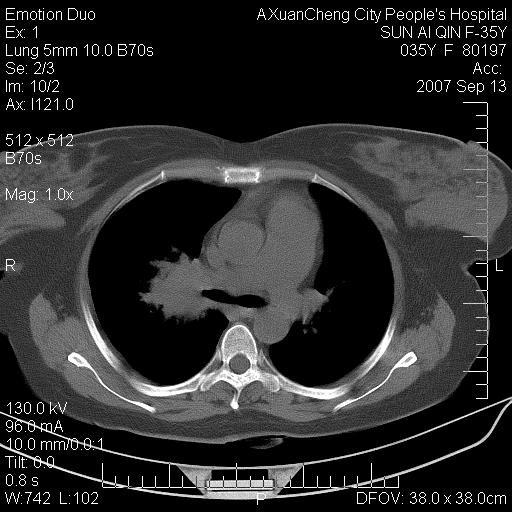

以下是引用天南地北在2007-9-13 13:43:00的发言:[br]考虑双肺、肺门侵润

以下是引用ydx_74在2007-9-13 15:42:00的发言:[br]仅看片,考虑右上肺癌并双肺转移,结合病史,考虑肺门、肺内淋巴侵润

以下是引用同在2007-9-13 15:08:00的发言:[br]支持肺门及双肺侵润.